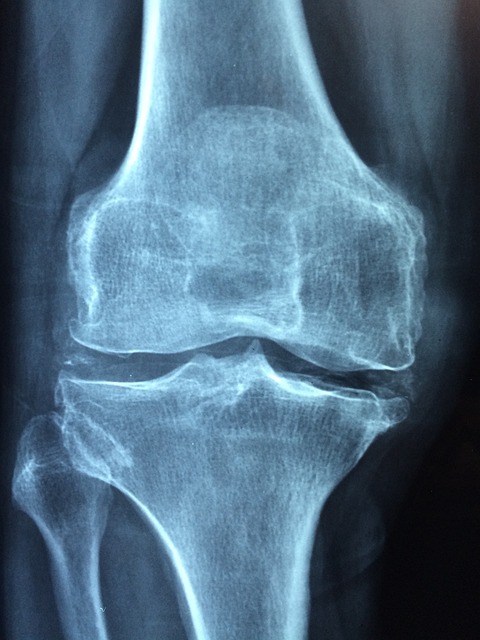

4.3 영상 검사

- X-ray

- 관절 공간의 축소, 연골 손상 확인.